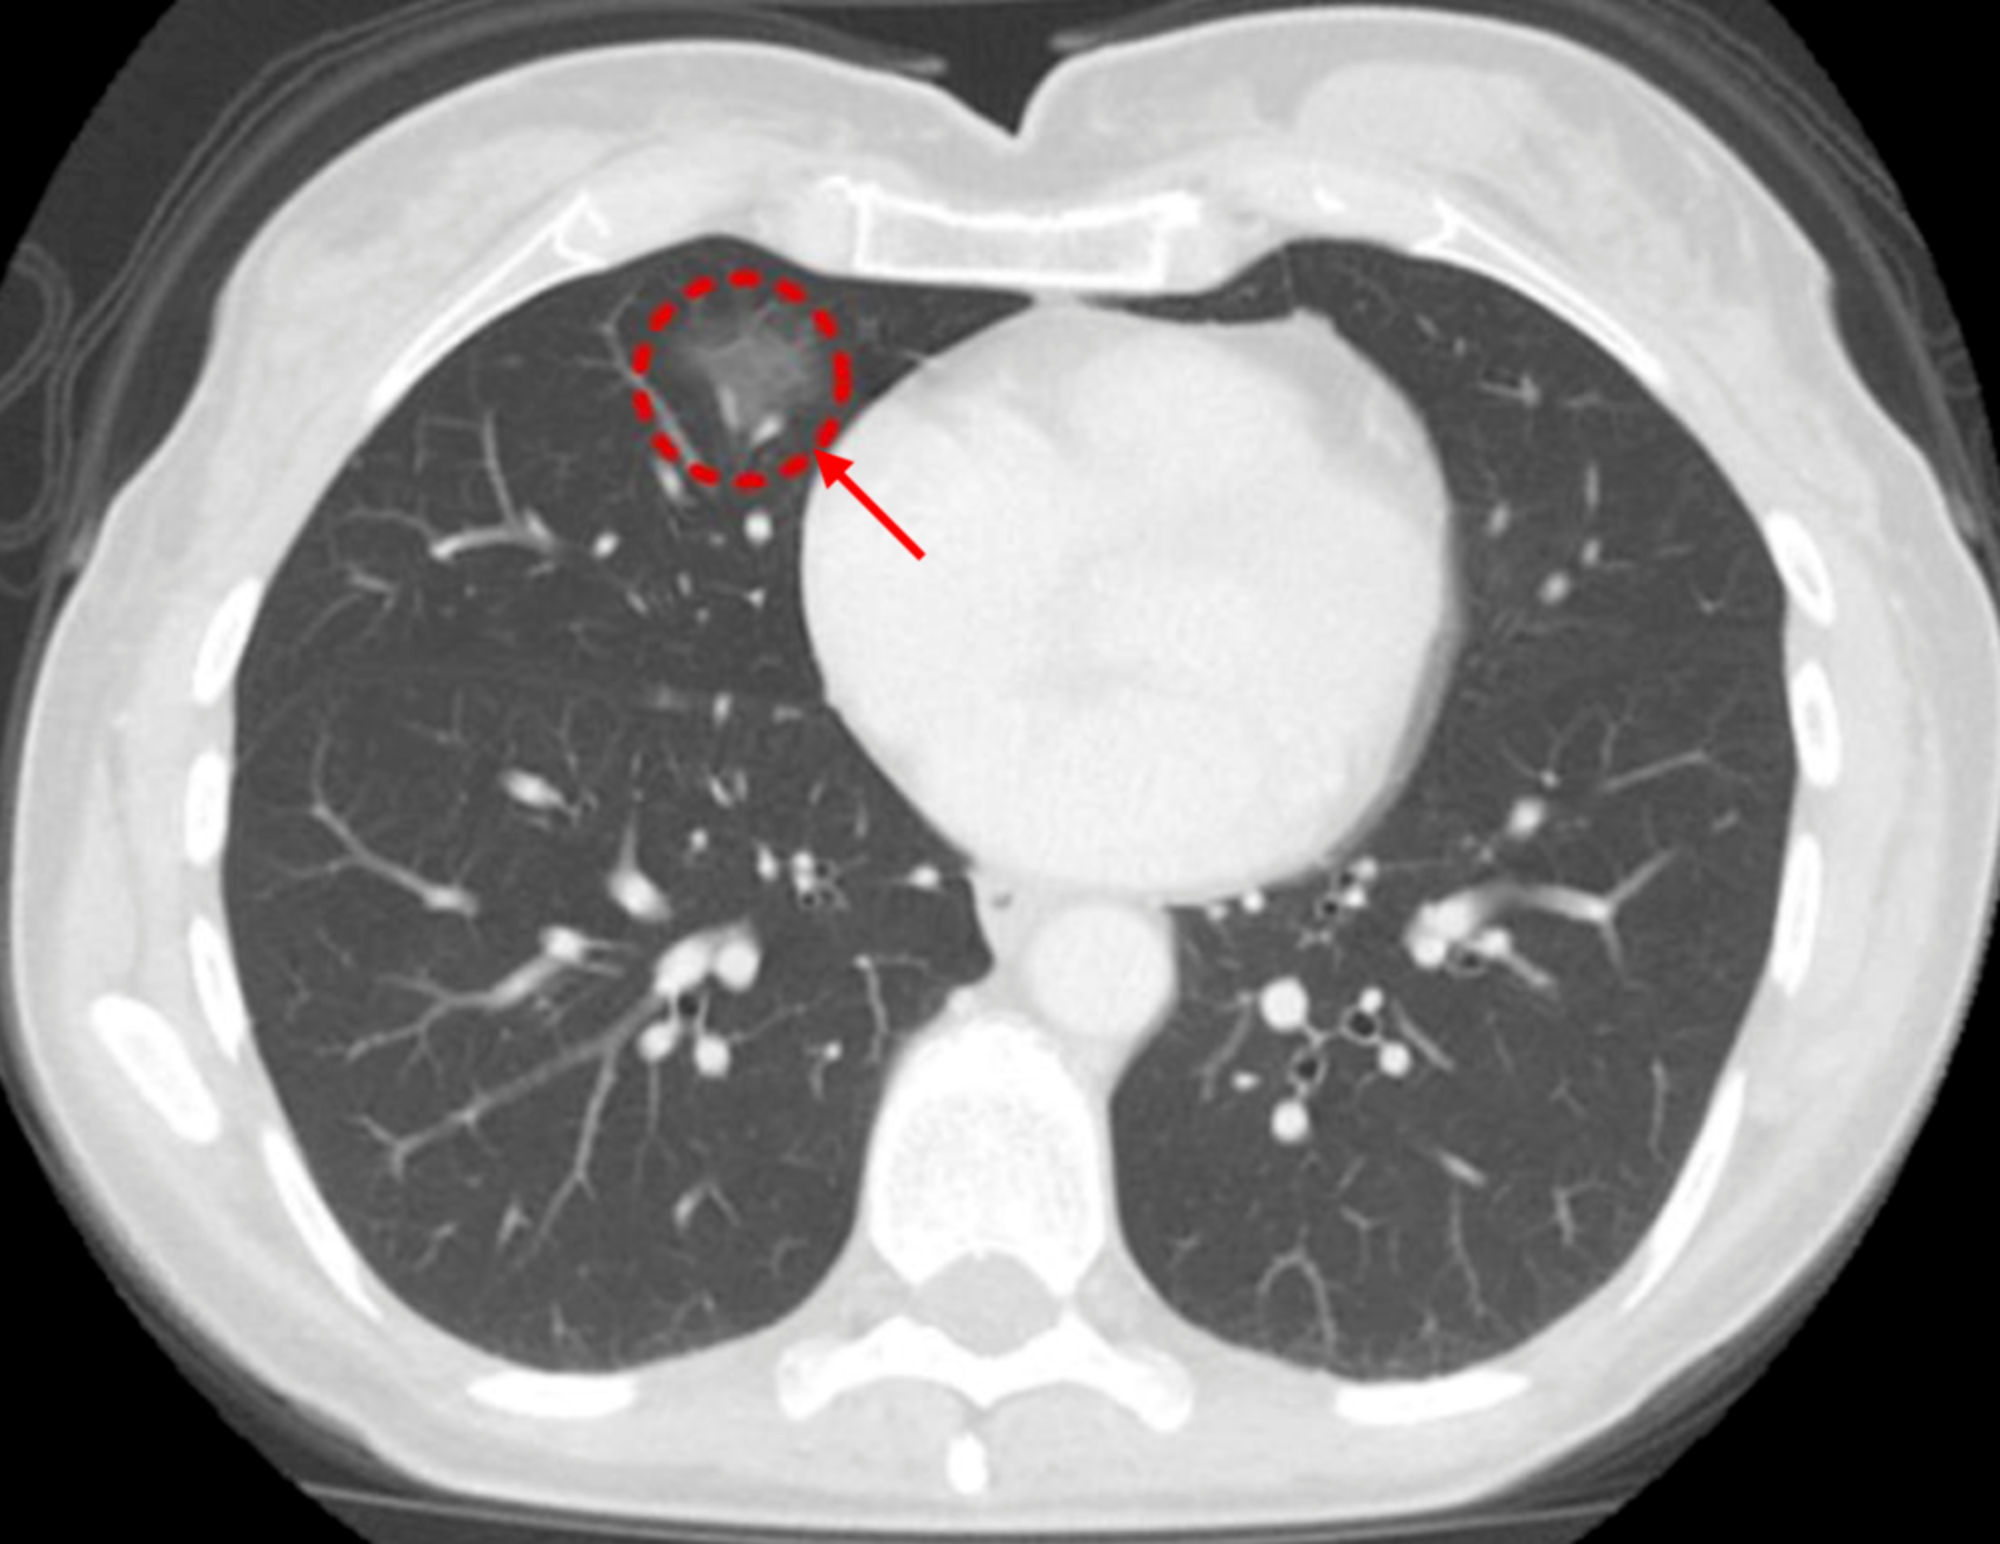

这个患者,单纯门诊定期随访,一年后结节不见了。